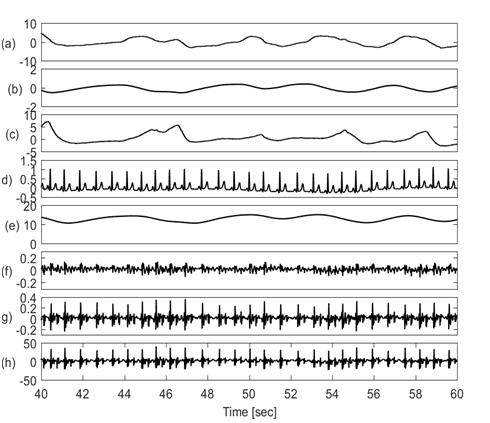

The goal of this study is to detect respiration information from various physiological signals including: chest wall movement, ECG, chest galvanic skin response (GSR) and SCG signals. All respiration signals considered will be compared with simultaneously acquired lung volume changes from direct respiration airflow measurements. This permits the identification of signals that best correlate with the direct respiration measurement. Figure 1 shows the physiological signals of interest plotted over a period of 20 seconds. The signals showed a period of oscillation that is potentially similar to the lung volume signal.

Figure 1 Physiological signals in time domain showing (a) Respiratory airflow, (b) Lung volume, (c) chest wall movement by piezo-electric sensor, (d) ECG, (e) Galvanic skin response, (f) SCG in craniocaudal axis, (g). SCG in lateral axis, (h) SCG in dorsoventral axis. All other signals (c to h) appear to potentially have components at the respiratory frequency, which indicates that respiratory information may be extracted from these signals.